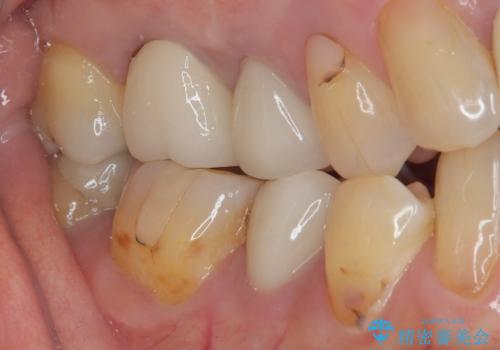

- 目立つ銀歯を気にして来院された患者様です。

奥歯を中心に銀歯が多く装着されており、一部の歯は咬合時に痛みを感じている状態でした。

必要な歯に根管治療を行い、オールセラミッククラウンにて補綴治療を行うこととしました。